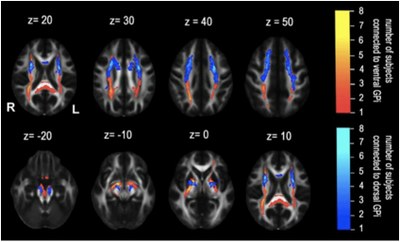

O artigo, na área de "Brain Imaging", refere-se ao tratamento utilizado em doentes com distonia (desordem do foro neurológico que causa perturbações no movimento). A estimulação cerebral profunda (“deep brain stimulation”) do Globo Pallidal Interno (GPI) é o tratamento normalmente utilizado nestes doentes. No entanto, e de acordo com o abstract do artigo, “há evidências de que a estimulação do GPI ventral e dorsal produz efeitos opostos a nível motor”. O objetivo do estudo foi, assim, analisar e comparar os perfis de conetividade do GPI ventral e dorsal com o córtex motor, tentando encontrar uma explicação para os efeitos encontrados.

“Trabalhámos as imagens multimodais de MRI (Magnetic Resonance Imaging) de doentes com distonia tratados com estimuladores de deep brain stimulation (DBS) e avaliámos para onde se projetavam no córtex as fibras cerebrais com origem junto aos elétrodos de estimulação”, explica o investigador João Paulo Cunha. Como resultado, os investigadores encontraram uma diferença significativa na distribuição ântero-posterior das fibras junto das áreas laterais corticais sensorio-motoras entre a conectividade GPI ventral e dorsal. A constatação de diferentes perfis de conectividade GPI-córtex confirma ainda a evidência clínica que os GPI ventral e dorsal pertencem a diferentes subsistemas motor funcionais e anatómicos. Ainda de acordo com o artigo, a consideração dos fatores anteriormente descritos poderá desempenhar um papel importante na promoção dos efeitos clínicos DBS em doentes com distonia.